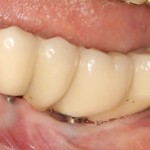

Нижние, вроде как, вполне держатся, на них стоят постоянные металлокерамические коронки. Помните, что я говорил про один из главных критериев качественной имплантологической работы? Состояние десны вокруг имплантов!

Хотите на это посмотреть? Этого не покажут, рекламируя базальную имплантацию:

То есть, друзья, десны нет. За подобную работу в наших клиниках рвут диплом в клочья и выгоняют нафиг. Для базальной имплантации, такая ситуация — норма:

И теперь представьте, как за всем этим ухаживать? Как этим жевать, если учесть тот факт, что ножка импланта, торчащая из десны, легко гнется? И сколько такие импланты вообще прослужат, если учесть сложную гигиену и неудобную форму протеза в этом участке?